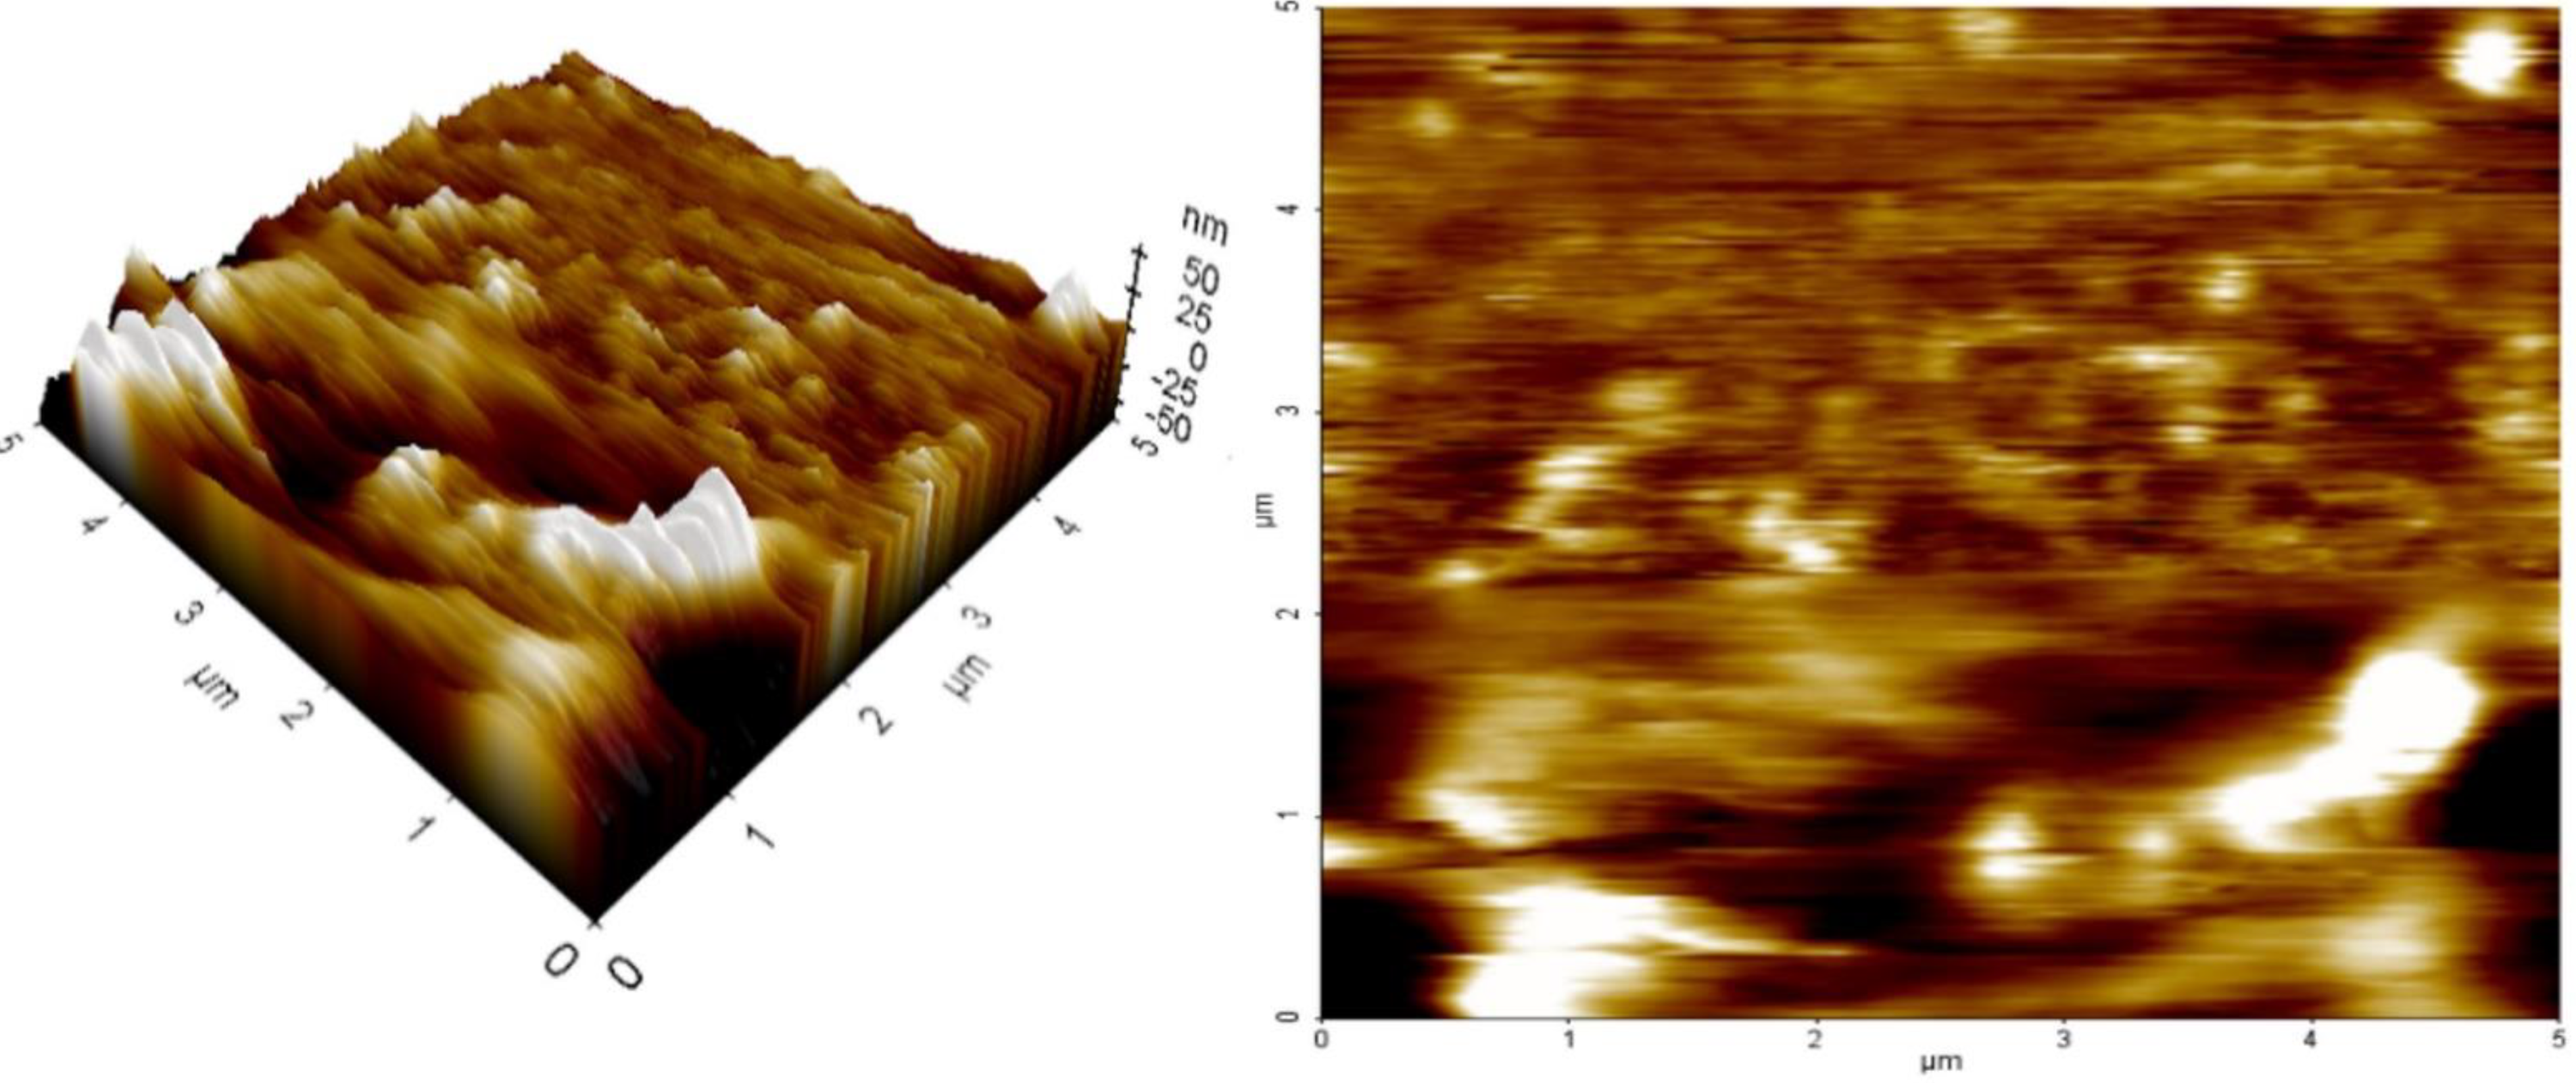

2.8. AFM

4.9.5. AFM